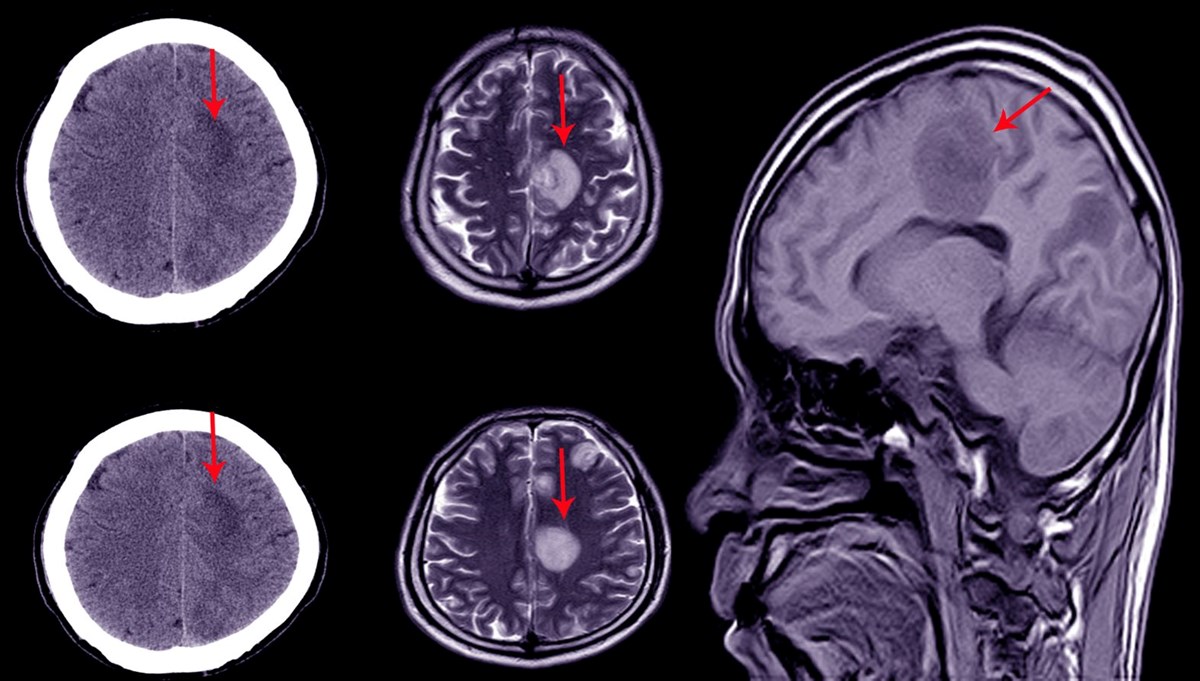

Beyninin yüzde 90'ı eksik olmasına rağmen nispeten normal ve sağlıklı bir hayat yaşayan bir adam, bilim dünyasını şaşkına çevirdi. Bu durum beyin ve bilinç hakkında mevcut anlayışların sorgulanmasıyla bilim dünyasında geniş bir etki yarattı.Beynimizin yalnızca yüzde 10'unu kullandığımız efsanesi bilim insanları tarafından kesin bir dille çürütüldü, ancak beyin hakkında hâlâ bilmediğimiz çok şey var.Bilim insanlarının onlarca yıldır kafasını karıştıran bir vaka da bunların başında geliyor.Yıllar önce kimliği bilinmeyen Fransız bir adamın beyninin yüzde 90'ının eksik olduğu ancak normal bir yaşam sürdüğü tespit edildi. Bu durum, beyin ve insan bilinci hakkında var olan bilgileri yeniden sorgulamaya yol açtı.2007 yılında The Lancet dergisinde yayımlanan bu hikaye, bilim dünyasında büyük bir yankı uyandırdı. 44 yaşındaki adam bacağında güçsüzlük hissi yaşaması üzerine doktora gitti. Yapılan muayenede, beyninin büyük bir kısmının kayıp olduğu ve kafatasının sıvı ile dolu olduğu belirlendi. Bu durum hidrosefali olarak biliniyor.Bilişsel psikolog Axel Cleeremans, adamın normal bir yaşam sürdüğünü, bir ailesi ve işi bulunduğunu belirtti. Adamın IQ testi 84 olarak ölçüldü. Normal aralığın biraz altında ancak bu durum adamın yaşamını etkilemedi.Çocukken bir stentle tedavi edilen adamın, stent çıkarıldıktan sonra beyninin büyük kısmı aşınmıştı. Beyin taramalarında, beyin dokusunun büyük kısmının sıvı ile dolduğu ve tahrip olduğu gözlemlendi.Cleeremans bu durumu "Beyin, bilinçle doğmuyor. Bilinç tekrar tekrar öğreniliyor. Daha sade bir ifadeyle; beyin, bir şekilde yaşamanın ve öğrenmenin yolunu buluyor" ifadeleriyle açıklıyor. Beynin sürekli ve bilinçsizce kendi etkinliğini kendisine yeniden tanımlamayı öğrendiğini ve bu açıklamaların bilinçli deneyimin temelini oluşturduğunu iddia ediyor.Bu durum, bilincin beyinle ilişkisi hakkındaki mevcut teorileri sorgulamaya yol açtı. Bilim insanları, belirli beyin bölgelerinin bilinçten sorumlu olmadığına dair yeni teoriler geliştirdi. Ayrıca, yetişkin beyinlerinin yaralanma durumunda farklı bölümlerin yeni roller üstlenebileceği öne sürülmektedir.